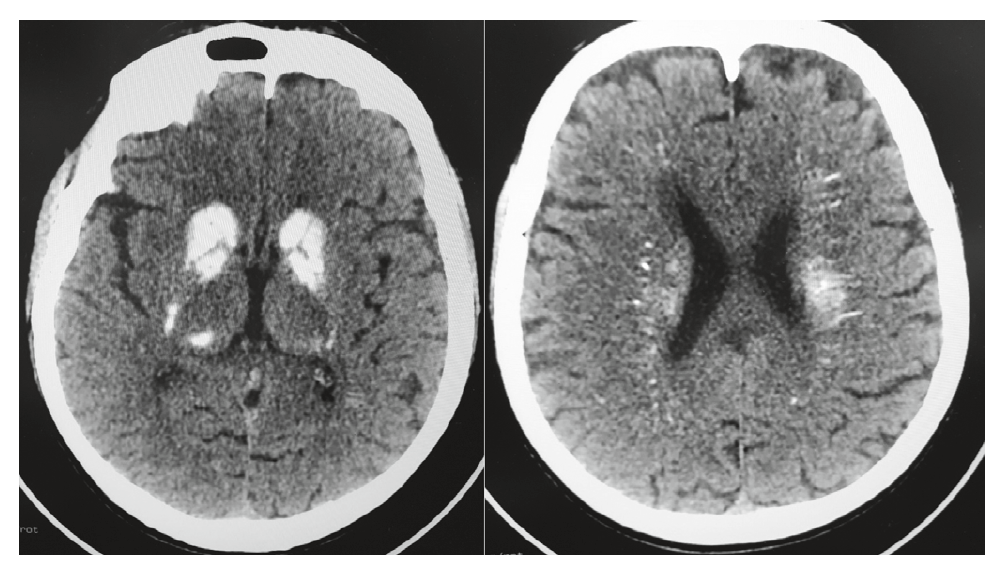

3. Fig. 1. MSCT of the brain. Note: Farah syndrome is a calcification of the basal ganglia (right) and nerve fibers (left). | |